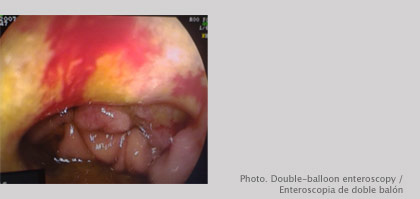

Double-balloon enteroscopy

What is Double-balloon enteroscopy?

Endoscopic method that allows intubation, visualization and diagnostic and therapeutic maneuvers of diseases located in the small intestine.Double-balloon enteroscopy